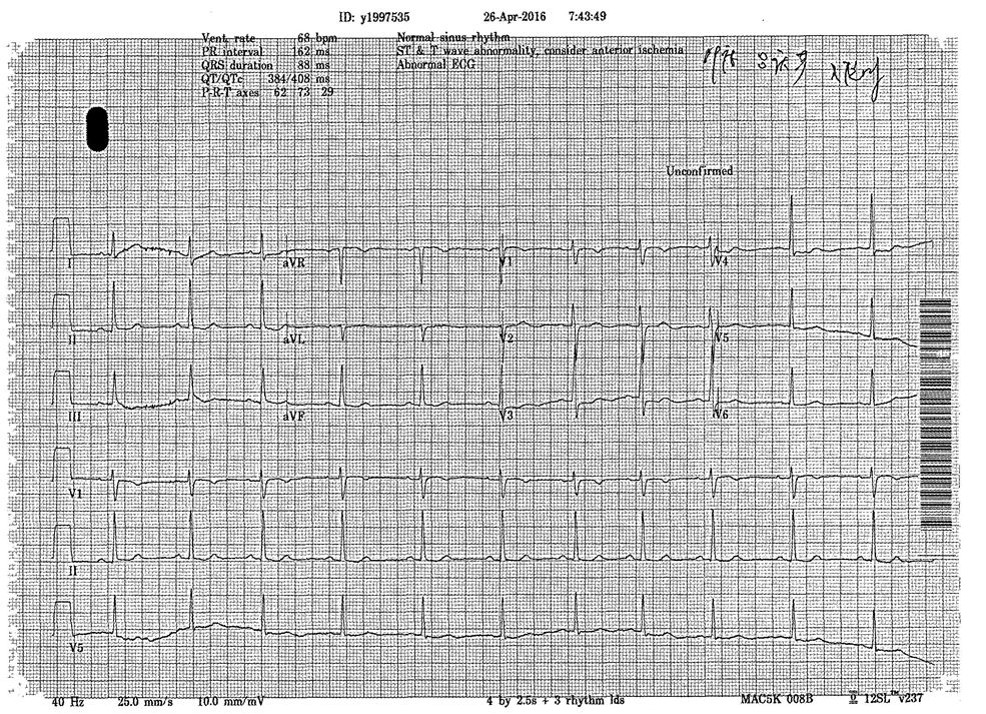

心电图

入院诊断

冠心病 不稳定性心绞痛